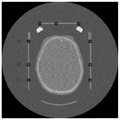

图2显示为本发明的中心位置点于一实施例中的示意图;FIG. 2 shows a schematic diagram of the center position point of the present invention in an embodiment;

如图2所示,在左侧有A、B和C三个轮廓中心位置点,选取B为参考点。B的相对高度为hr=lλ,其中,As shown in Figure 2, there are three contour center points A, B and C on the left side, and B is selected as the reference point. The relative height of B is hr =lλ , where,